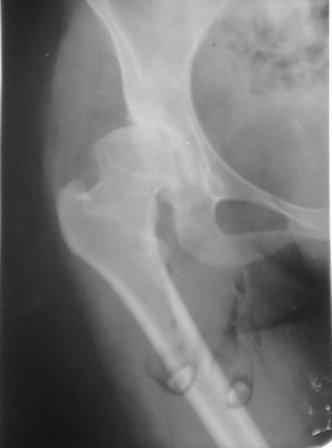

Представляю Р-снимки: обзорная, с отведением и с приведением.